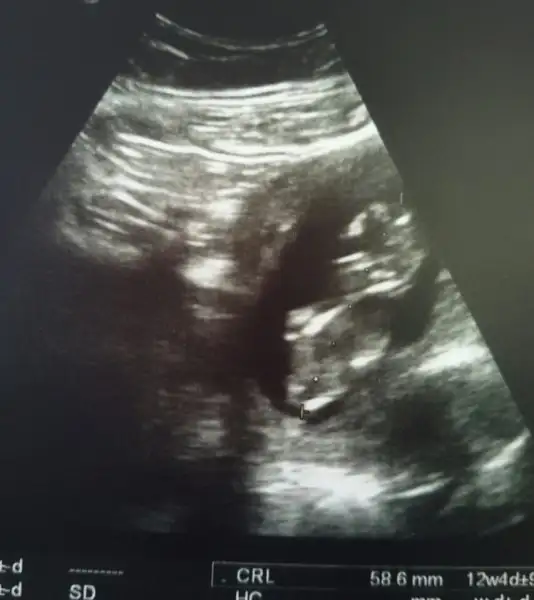

Ya kızlar ama kimse yorum yapmıyoo tahminleri bekliyorumEki Görüntüle 2062680 başardım sonunda resim yüklemeyi

canım seninkinin görüntüsünü tam önden almış nub u hiç belli olmuyor ama yuvarlacık kafası sivri gelen çene kemiği bana kızı düşündürttü içimden geçen oYa kızlar ama kimse yorum yapmıyoo tahminleri bekliyorumsofiarya senden özellikle bi tahmin bekliyorum